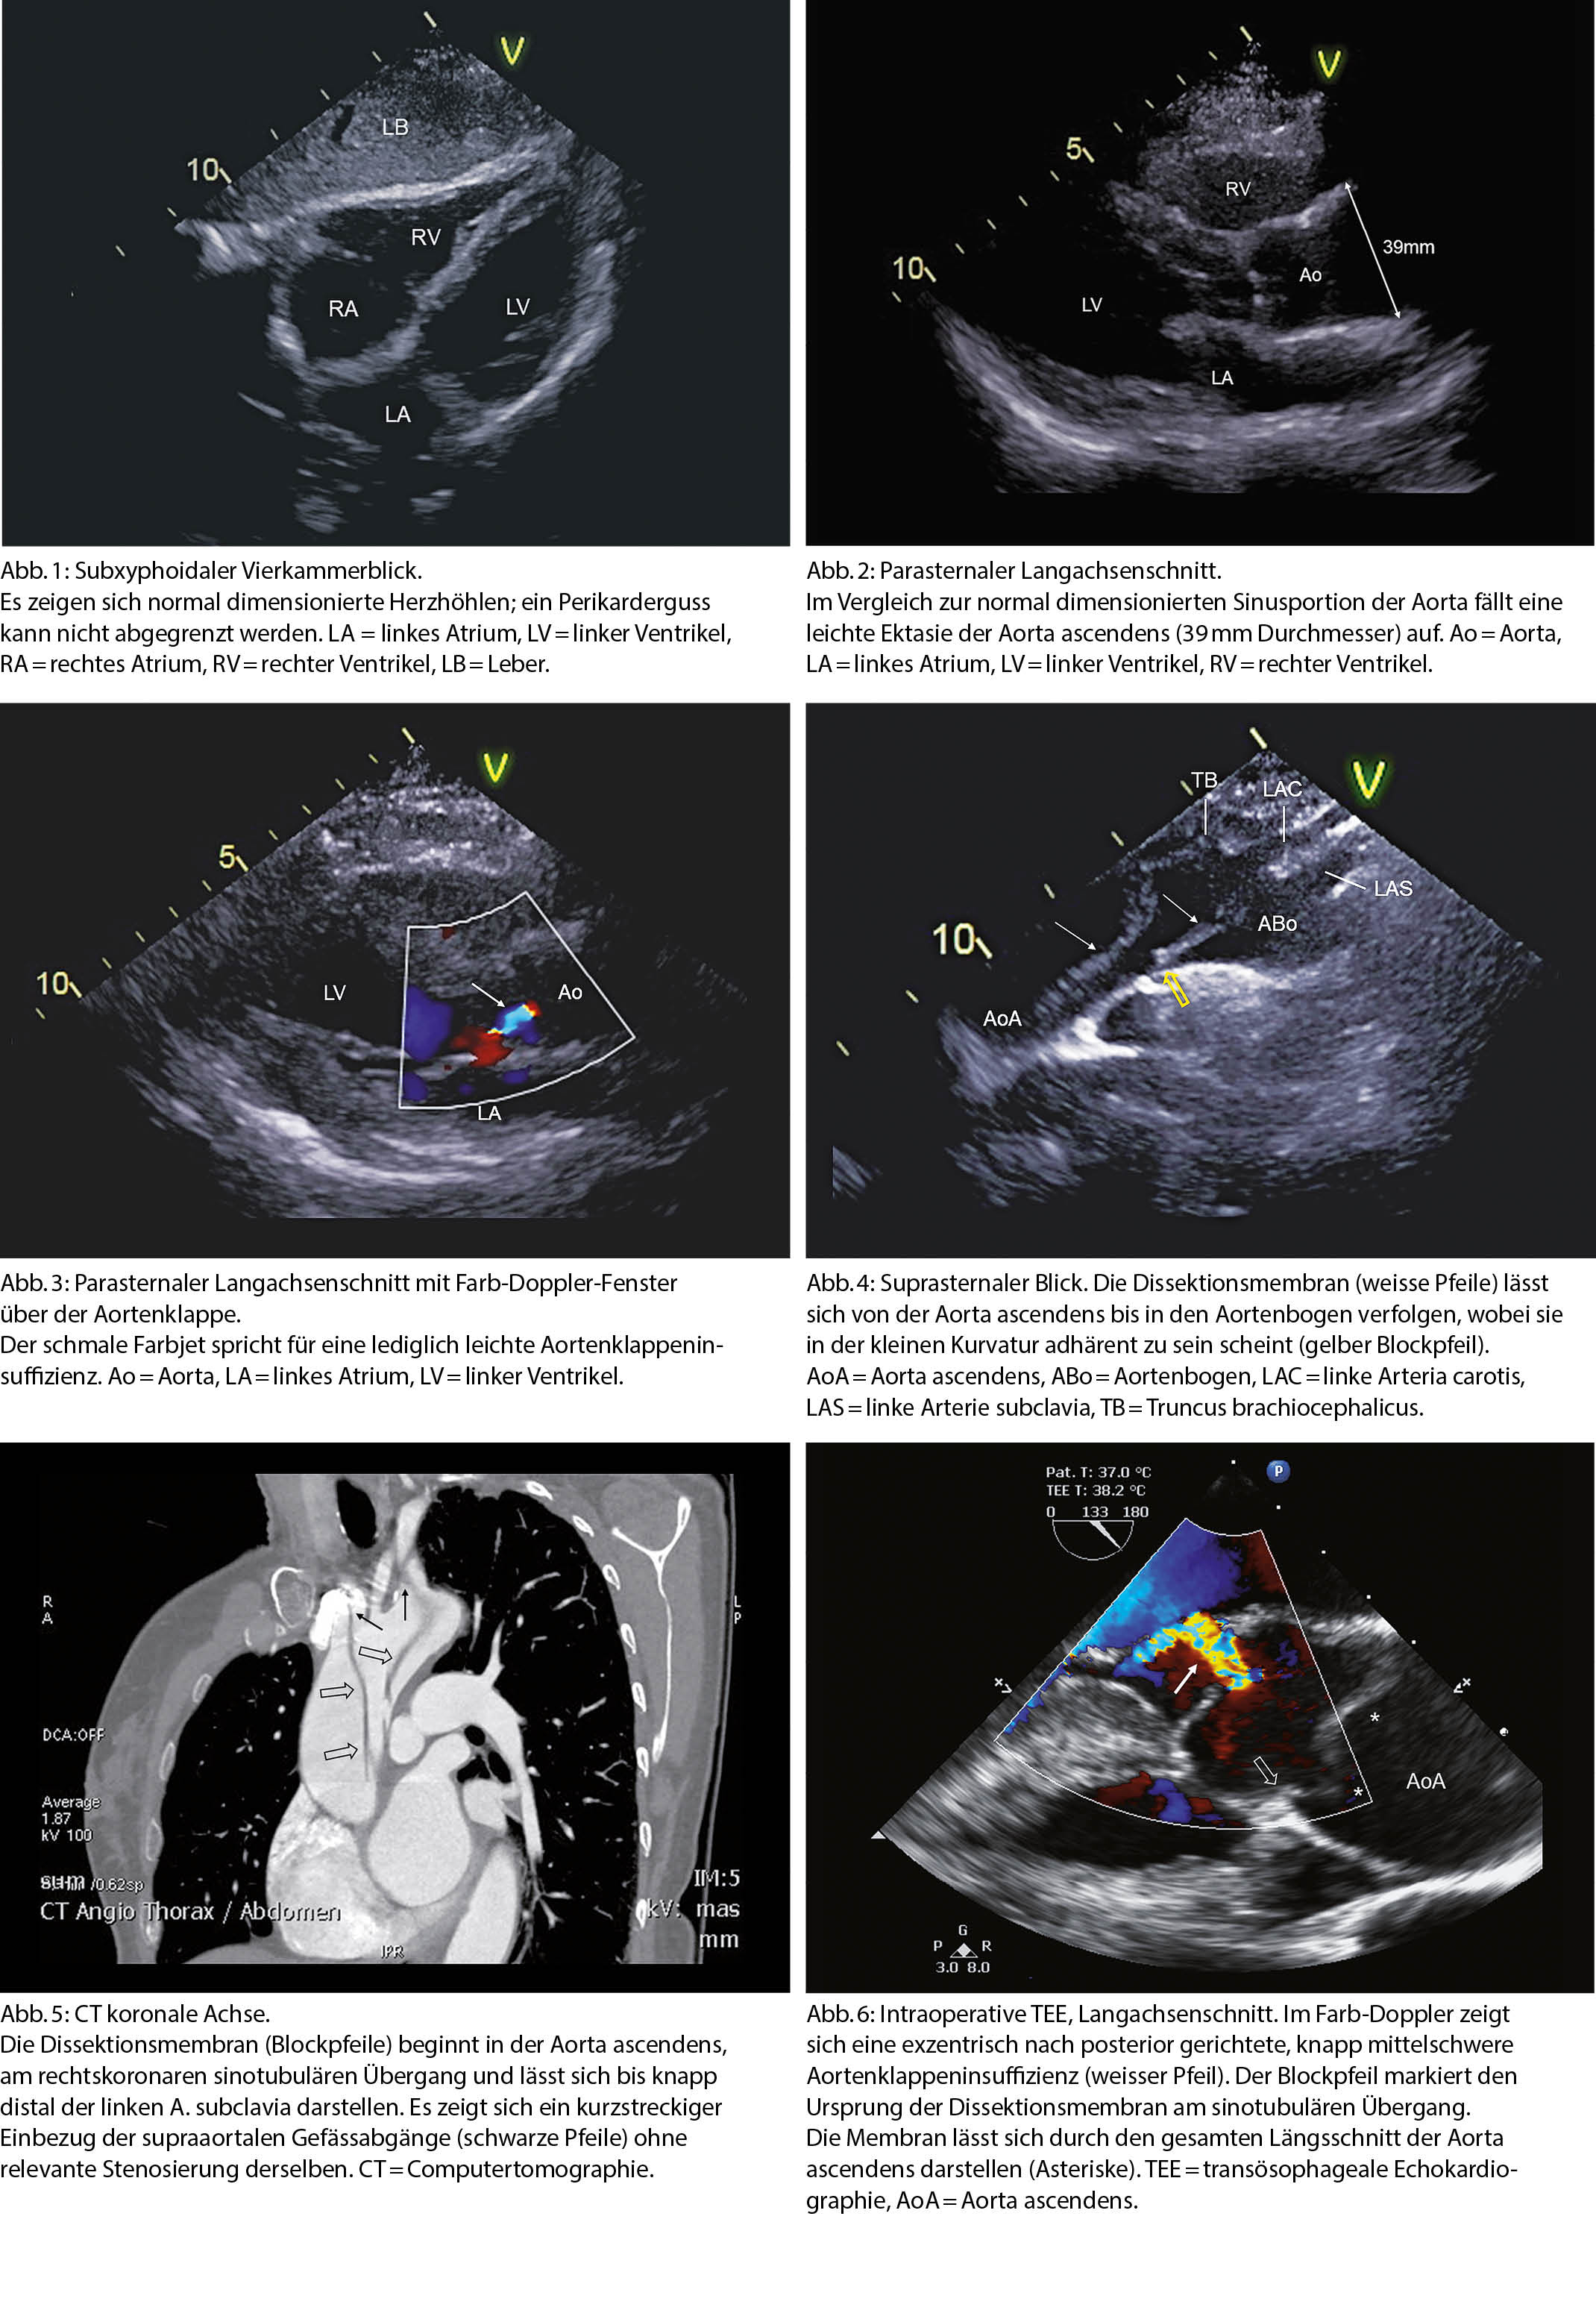

Eine 61-jährige Patientin wurde mit der Sanität auf die Notfallstation gebracht, nachdem sie beim Joggen plötzlich starke thorakale Schmerzen mit Ausstrahlung in den Rücken und zum Hals beklagte. Bei einem systolischen Blutdruck von 70 mmHg erfolgte die Erstbeurteilung im Schockraum. Bei der klinischen Untersuchung fiel eine Wortfindungsstörung auf. Das Ruhe-EKG zeigte einen unauffälligen Befund. Die diensthabende Kardiologin wurde in den Schockraum gerufen, um eine fokussierte transthorakale Echokardiographie (TTE) durchzuführen. Hierbei zeigte sich eine hyperdyname linksventrikuläre Pumpfunktion ohne Anhaltspunkte für regionale Kinetikstörungen. Ebenso bestanden weder Hinweise für einen Perikarderguss, noch für eine akute Rechtsherzbelastung (Abbildung 1). Im Gegensatz zu der normal dimensionierten Sinusportion war die Aorta ascendens leicht ektatisch erweitert (Abb. 2). In der Aorta ascendens fiel wiederholt eine flottierende Struktur auf, welche im Kontext verdächtig auf einen Intimaflap einer Aortendissektion war. Die Aortenklappe zeigte im Farb-Doppler eine leichte Insuffizienz (Abb. 3). Die Darstellung der proximalen Aorta von suprasternal konnte den Verdacht auf eine Aortendissektion Typ A bestätigen. Die Dissektionsmembran liess sich von der Aorta ascendens bis in den Aortenbogen nachweisen (Abb. 4). Somit konnte innerhalb weniger Minuten die Diagnose einer Aortendissektion Typ A gestellt und die Kollegen der Herzchirurgie konnten informiert werden. Zur genaueren Beurteilung der Ausdehnung und ergänzenden präoperativen Planung wurde noch im Schockraum eine Computertomographie (CT) durchgeführt, bei welcher sich eine Ausdehnung der Dissektion von der Sinusportion bis in den Aortenbogen knapp distal der linken A. subclavia zeigte und eine Fortsetzung der Dissektion bis in die Abgänge der supraaortalen Gefässe zur Darstellung kam (Abb. 5). Die Patientin wurde in der Folge notfallmässig operiert. Auch in der intraoperativen transösophagealen Echokardiographie (TEE) liess sich die Dissektionsmembran mit Ursprung am sinotubulären Übergang der Aorta gut darstellen. Die Aorteninsuffizienz war exzentrisch nach posterior gerichtet und im TEE knapp mittelschweren Grades (Abb. 6). Es konnte eine klappenerhaltende Operation mittels eines suprakoronaren Graftersatzes durchgeführt werden. Der postoperative Verlauf war insgesamt erfreulich und die Patientin konnte nach 16 Tagen in eine stationäre Rehabilitation entlassen werden.